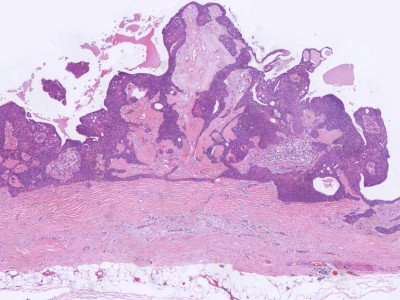

![Histologie hidradenoma (click on photo to enlarge) [source: Kevin Kwee / Afdeling Pathologie MUMC] Histologie hidradenoma](../../../pacoupes/thumbnails/hidradenoma.jpg) |

ingescande coupe (zoom) |

Bron

hoge resolutie PA-foto's: Kevin Kwee en Afdeling Pathologie MUMC. Klik

op de afbeelding om in te zoomen.